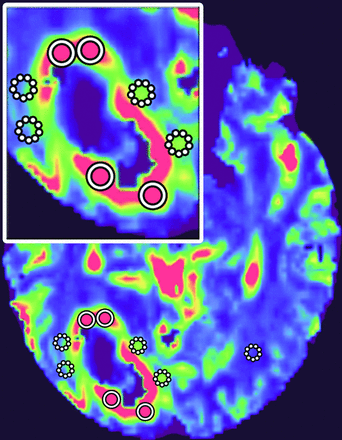

Color-coded iVASO-CBVa and DSC-CBV maps were generated, respectively. The region of maximal abnormality of each parameter within the lesion volume (hotspot) was determined via visual inspection. This methodology was demonstrated to provide the most optimal interobserver and intraobserver reproducibility.33 Four ROIs of about 20 pixels were carefully placed on the hotspots, respectively, in the intratumoral region and the peritumoral T2-hyperintense region (PTH), to obtain the maximum iVASO-CBVa and CBV of each region. The PTH was defined as the T2-hyperintense region within 1 cm around the enhancing tumor.13 ROIs were drawn in the contralateral white matter as references for normalization (iVASO-rCBVa and DSC-rCBV) (Fig 1). All ROIs were placed independently by 2 blinded experienced neuroradiologists (X. Li and Y. Wu, with 5 and 12 years of experience, respectively). The measurement results of the 2 radiologists were used to assess the interobserver reliability. The average of the 2 measurement results was used for further statistical analysis.

ROI placements. Four to six ROIs were drawn in both intratumoral (circle with solid line) and peritumoral (circle with dotted line) regions, and the maximum value was recorded. Also, an ROI in the contralateral white matter (circle with dotted line) was chosen as a reference. The insert is the magnification of lesion area.